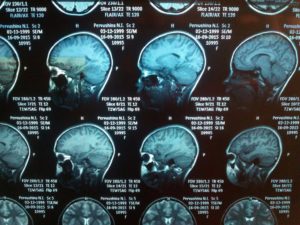

На снимках МРТ ткани обозначаются светлыми и темными участками. У структур мозга серый цвет, у внутримозговых синусов – черный. Светло-серые ручейки – это протекающие церебральные жидкости.

Преподаватели клинических ординатур знакомят студентов с базовыми особенностями магнитно-резонансной томографии:

- Снимки просматриваются перед световым источником;

- Мозговые ткани на снимке серого цвета;

- Церебральная жидкость – это «серые» ручейки;

- Внутримозговые синусы – черные полости.

Как выглядит на снимке мозг здорового человека?

МРТ головы помогает получить снимки, на которых ткани обозначены затемнениями и просветлениями. Ткани мозга имеют серый цвет. Протекающие церебральные жидкости отображаются в виде ручейков светло-серого оттенка. Черные полости на изображении — это внутримозговые синусы.